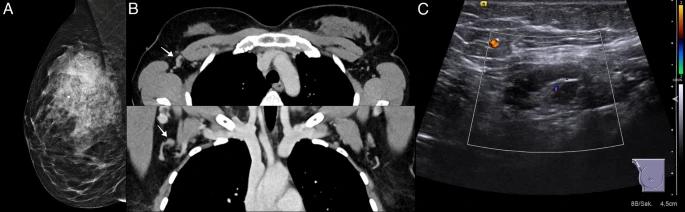

A new survey study from the American Cancer Society shows a 4.47 million decrease in cervical cancer screenings and a 2.13 million decrease in breast cancer screenings in the United States between 2018 and 2020.